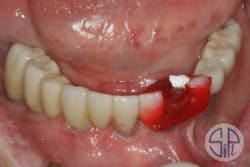

Following this verification step, a zirconia restoration was fabricated and delivered (figure 4). While screwing the restoration into place, a cracking sound was heard. The restoration had fractured lingually to the access hole of dental implant No. 27 (figure 5).

Figure 5: A fracture occurred in a lingual direction to the access hole of dental implant No. 27